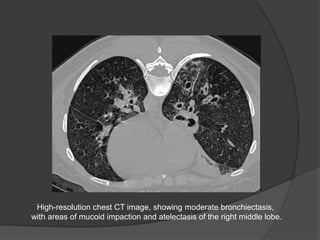

High-resolution chest CT image, showing moderate bronchiectasis,

with areas of mucoid impaction and atelectasis of the right middle lobe.